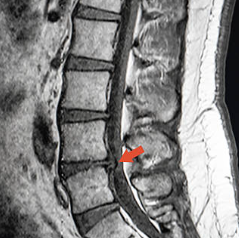

처음 방문한 곳은 정형외과였습니다. 의사 선생님은 간단한 신체 검사를 통해 허리를 앞으로 숙이게 하고 다리를 들어 올리는 테스트를 진행했습니다. 이 과정에서 다리 신경이 당기면서 통증이 뚜렷해졌고, 허리디스크 가능성이 높다고 판단되었습니다. 이후 MRI 검사를 받았는데, 디스크가 튀어나와 신경을 누르고 있다는 소견을 받았습니다. 화면에 선명하게 보이는 돌출된 디스크를 보니 그동안의 통증이 왜 발생했는지 이해할 수 있었습니다.